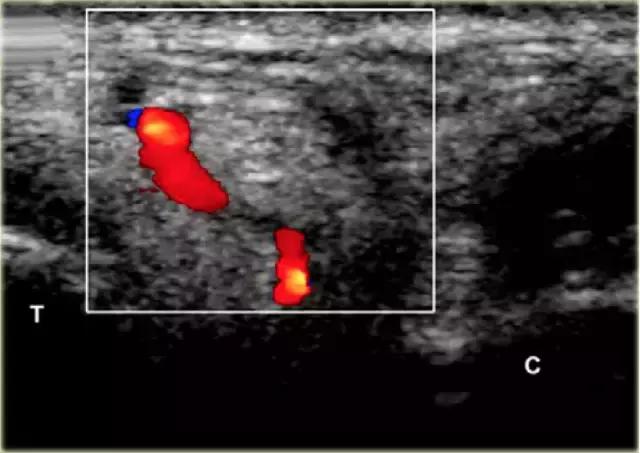

使用超声波可以容易地视察窦性骨壁。患者转向对侧,将待治疗的足以其内侧表面靠在桌面上,脚的外侧位于最上面。探头保持在关于脚的冠状平面中。

在跗骨窦被识别为跟骨的前处理和距骨颈之间的三角空间。针(箭头)的前端的锥形跗骨窦,这是由距骨(T)和跟骨(C)的边界内可以看到。

根据炎症的程度,可能存在空间的充血,并且可能存在中间血管可见,这是人们希望避免的。但是这又是比较容易的,特别是彩色多普勒。